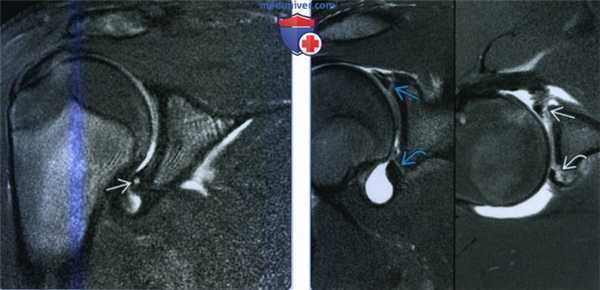

(Слева) На рисунке показан передний и задний разрыв верхней губы V типа. Имеется разрыв верхней губы, который расширяется до разрыва Банкарта. Это самый частый тип расширенного переднего и заднего разрыва верхней губы, который наблюдается у 20% пациентов с разрывом Банкарта и у 15% пациентов с передним и задним разрывом верхней губы II-XII типа.

(Справа) На фронтальной (слева) и осевой (справа) МР-артрограммах Т1ВИ определяется передний и задний разрыв верхней губы V типа. Передний и задний разрыв верхней губы расширяется вниз до разрыва Банкарта с утечкой контраста из сустава. У этого пациента после переднего вывиха возникла передняя нестабильность. (Слева) На рисунке показан передний и задний разрыв верхней губы VI типа. Это лоскутный разрыв верхней губы, при котором верхняя губа с передним и задним разрывом по всей ширине отделена на одном конце. Передний и задний разрыв верхней губы VI типа, в сущности, не является расширенным передним и задним разрывом верхней губы с захватом окружающей структуры, однако он описан после первичной классификации переднего и заднего разрыва верхней губы I-IV типа.

(Справа) На фронтальной МР-артрограмме Т1ВИ FS визуализируется отделенная верхняя губа. На операции был выявлен передний и задний разрыв верхней губы VI типа, поскольку один конец сегмента губы был отделен (не показано). (Слева) На рисунке показан передний и задний разрыв верхней губы VII типа, который переходит вниз на среднюю суставно-плечевую связку. Средняя суставно-плечевая связка начинается от передневерхней губы ниже верхней суставно-плечевой связки и двуглавой мышцы и затем прикрепляется ниже передней капсулы (не показано).

(Справа) На осевой МР-артрограмме Т1ВИ FS виден разрыв средней суставно-плечевой связки и передневерхней губы от нижнего расширения переднего и заднего разрыва верхней губы (не показано). Передние и задние разрывы верхней губы VII типа могут образоваться в результате падения на вытянутую руку. (Слева) На рисунке показан передний и задний разрыв верхней губы VIII типа с расширением до обратного разрыва Банкарта. Передние и задние разрывы верхней губы VIII типа составляют примерно 5% от всех передних и задних разрывов верхней губы II-XII типа и обычно образуются при заднем вывихе.

(Справа) На фронтальной (слева) и осевой (справа) МР-артрограммах Т1ВИ FS определяется передний и задний разрыв верхней губы с переходом в разрыв задней губы. У этого пациента отмечены симптомы нестабильности после предшествующего заднего вывиха. Кроме того, имеется небольшое повреждение хряща, прилежащею к обратному разрыву Банкарта. (Слева) На рисунке показан передний и задний разрыв верхней губы IX типа на 350° с расширением до разрыва Банкарта и обратного разрыва Банкарта с коротким сегментом интактной губы. Передние и задние разрывы верхней губы IX типа расширяются вниз до разрыва Банкарта и обратною разрыва Банкарта и обычно захватывают 2 70-360° губы. Эти разрывы видны примерно в 5% случаев от всех передних и задних разрывов верхней губы II-XII типа.

(Справа) На фронтальной (слева) и осевой (справа) Т1ВИ FS МР-артрограммах определяется передний и задний разрыв верхней губы IX типа, переходящий на переднюю и заднюю губу, но не затрагивающий нижнюю губу. (Слева) На рисунке показан передний и задний разрыв верхней губы XI типа, переходящий на верхнюю суставно-плечевую связку. Некоторые из таких разрывов также могу сопровождаться разрывом капсулы ротаторною интервала, который затем становится передним и задним разрывом верхней губы X/XI типа.

(Справа) На сагиттальной МР-артрограмме Т1ВИ FS определяется частичный разрыв верхней суставно-плечевой связки. На операции разрыв оказался продолжением переднею и заднею разрыва верхней губы (не показан), что относит ею к переднему и заднему разрыву верхней губы XI типа. Передний и задний разрыв верхней губы также перешел на сухожилие двуглавой мышцы, поэтому он, фактически, отнесен к переднему и заднему разрыву верхней губы IV/XI типа.